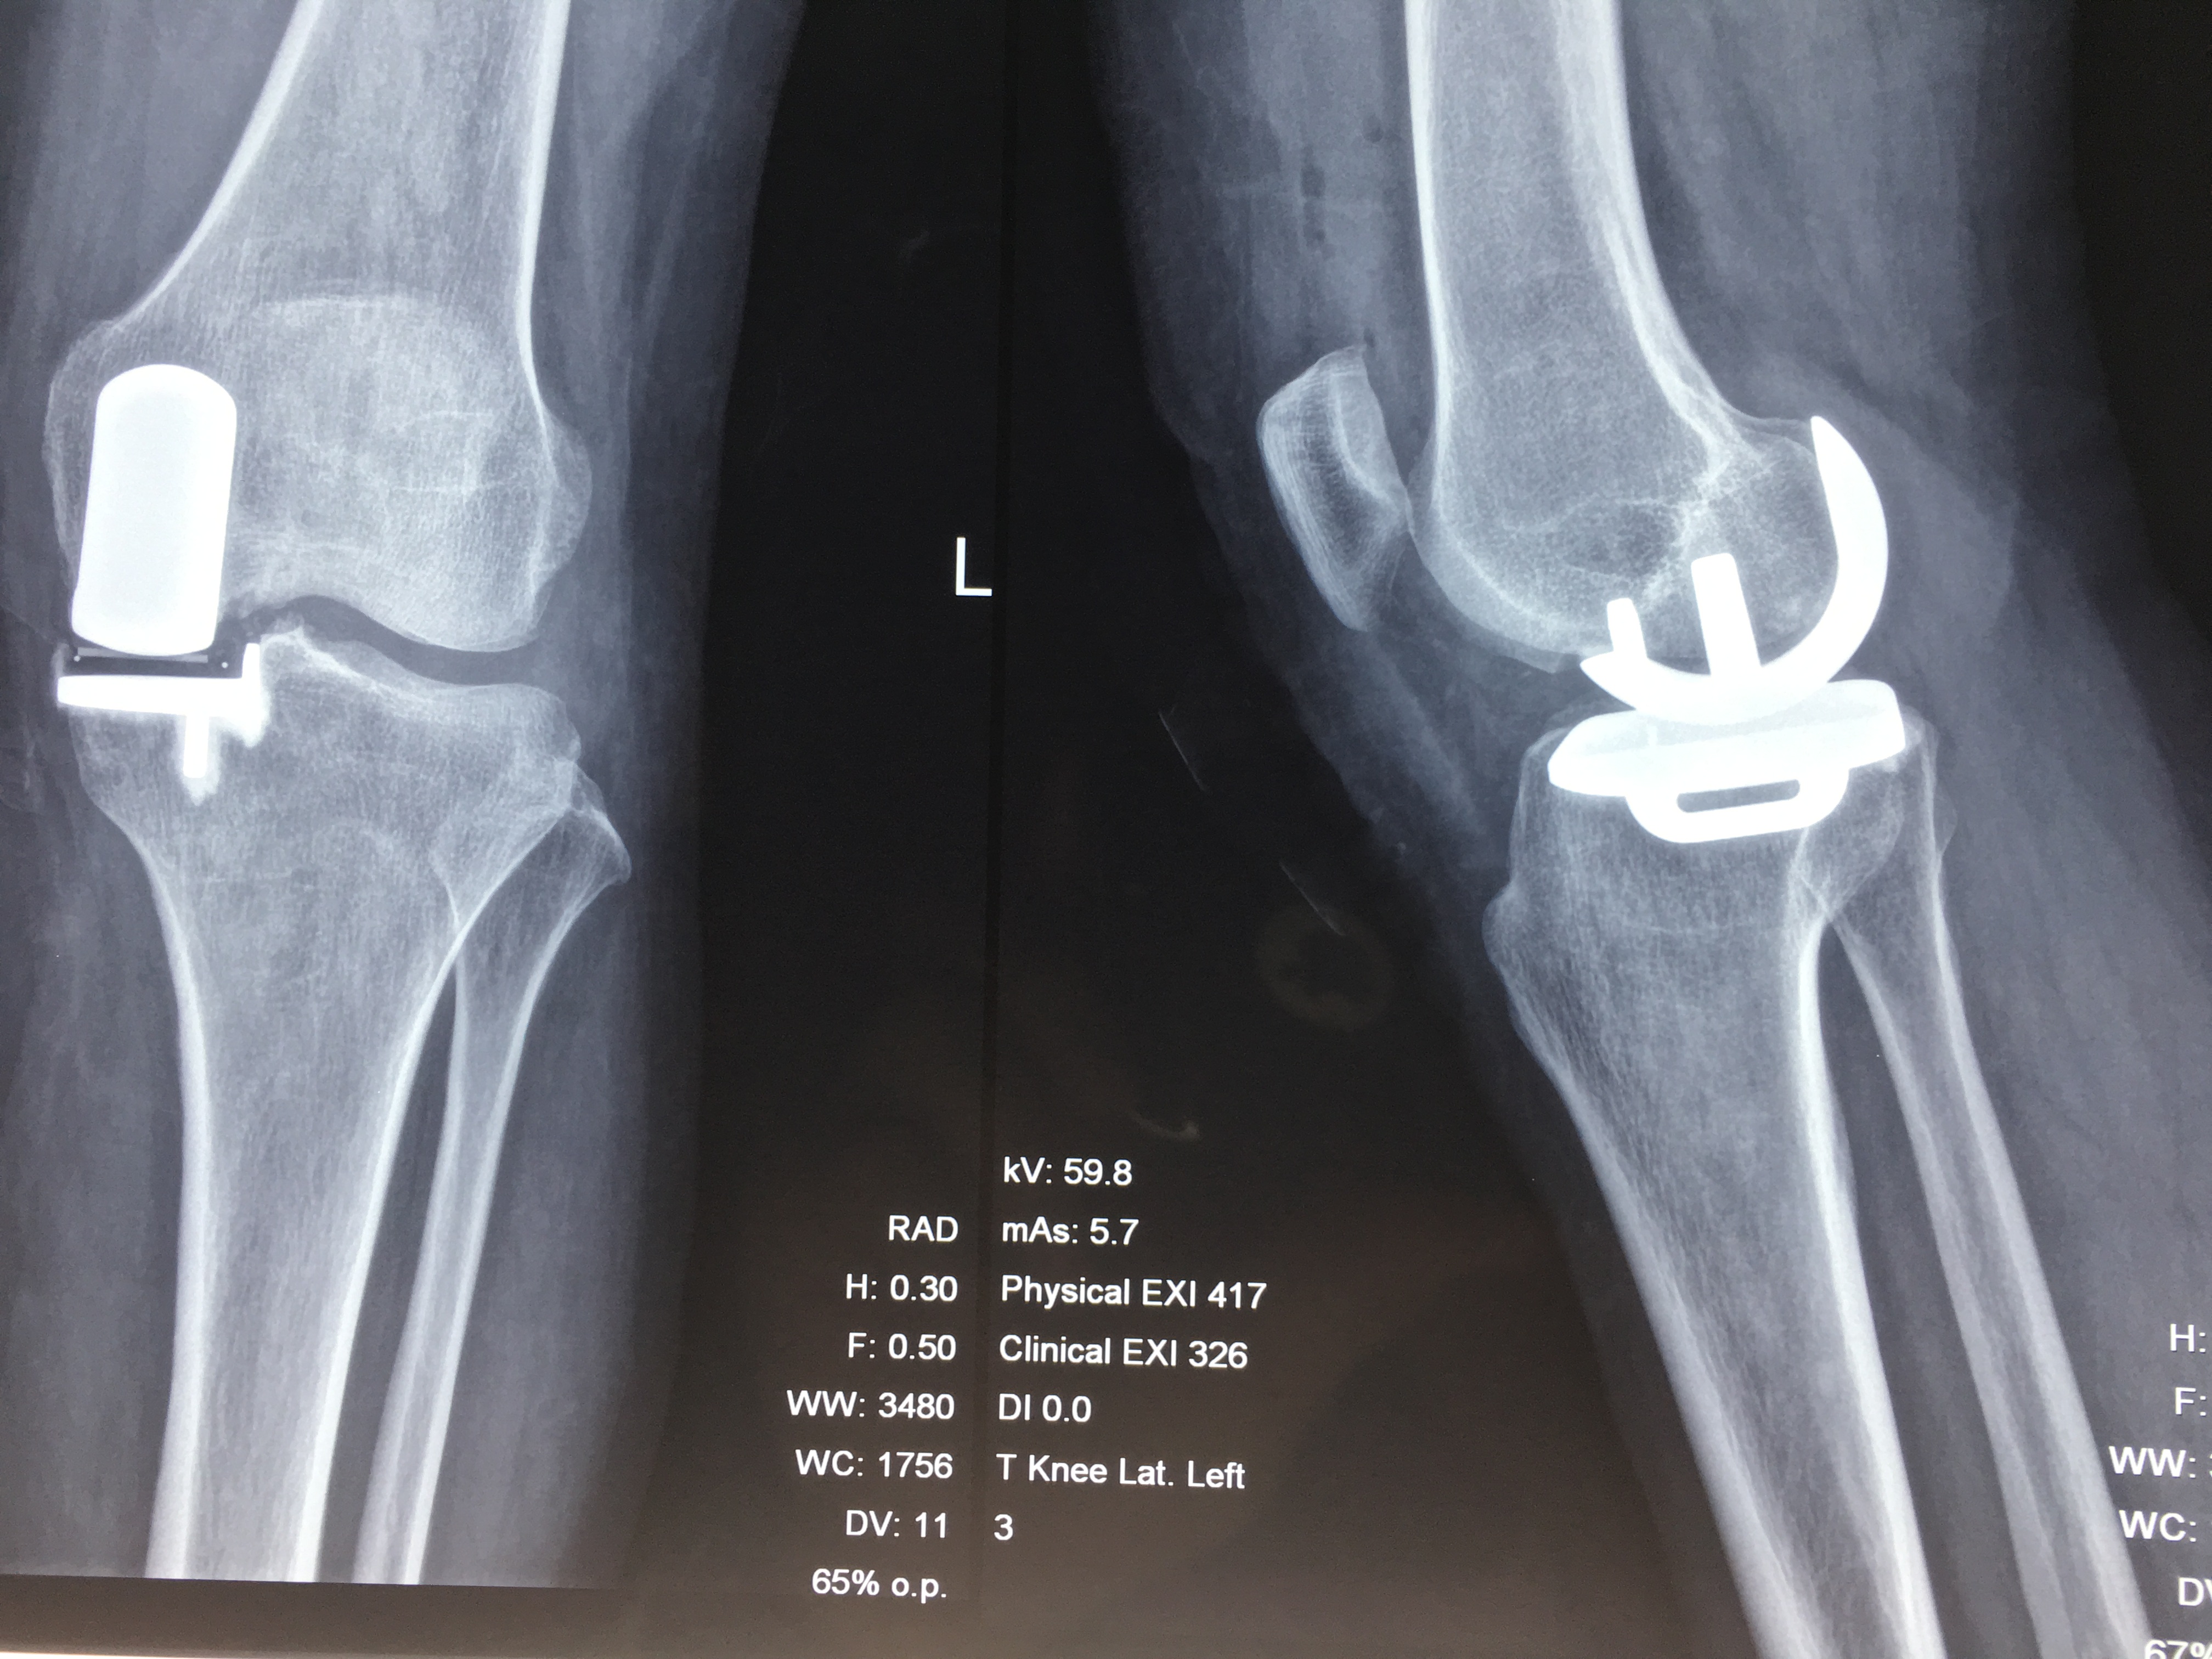

我院成功开展甘肃省首例牛津单髁膝关节置换术

我院骨三科于2017年成功自主开展我省首例牛津单髁关节置换术,目前已成功进行3例。单髁置换术具有损伤小、出血少、康复快、膝关节功能恢复良好、术后第二天即可下床、患者住院时间短、住院费用低等优势,为骨关节炎患者带来了福音。

单髁置换术只对病变的膝关节单间室进行置换,更加精准,尽可能保留了关节的自身结构和关节内的韧带(尤其前交叉和后交叉),保留了患者的本体感觉;同时单髁置换术相比全膝置换术治疗费用更低,术后膝关节功能恢复更好。

需要注意的是,不能将单髁置换理解为全膝置换的过渡性治疗。对于一部分患者,单髁置换治疗后可完全摆脱骨性关节炎的困扰,完全不需要再行全膝关节置换术。